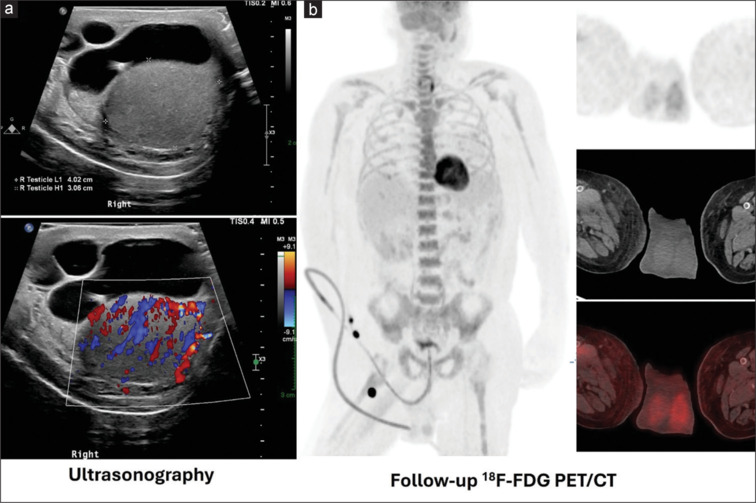

False positive findings in 18F-fluorodeoxyglucose positron emission tomography-computed tomography (18F-FDG PET/CT) scans can present challenges in the accurate diagnosis and staging of various conditions. We report a case of a 52-year-old male with known adenocarcinoma of the stomach who underwent total gastrectomy and chemotherapy and was referred for 18F-FDG PET/CT to rule out recurrence. 18F-FDG PET/CT showed a large FDG-avid lesion involving the entire right testicle mimicking testicular cancer or lymphoma. Further evaluation with ultrasonography revealed epididymo-orchitis, possibly of granulomatous etiology. Orchitis, an inflammatory condition of the testicles, can cause misleading results in 18F-FDG PET/CT imaging for cancer surveillance. Imagers should cautiously interpret PET/CT findings, considering clinical context, patient history, and additional imaging modalities to distinguish true malignancies from false positives.